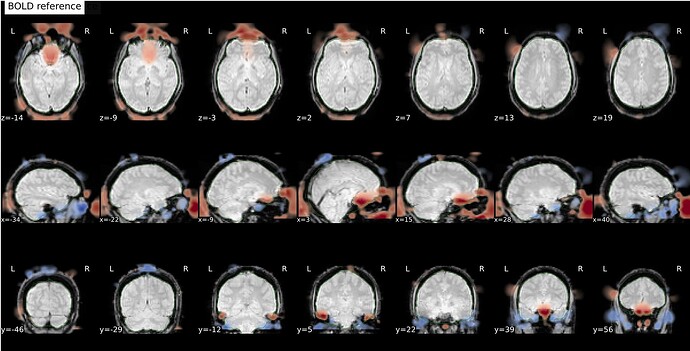

I’m seeing an apparent misalignment in the fmapCoreg reportlet for a PEPOLAR (SE-EPI AP/PA) distortion-correction workflow

- Raw AP/PA fieldmaps and raw BOLD data are perfectly aligned in native space.

- qform/sform matrices, voxel sizes, orientation, PE direction, and readout times all match across AP, PA, and all BOLD echoes.